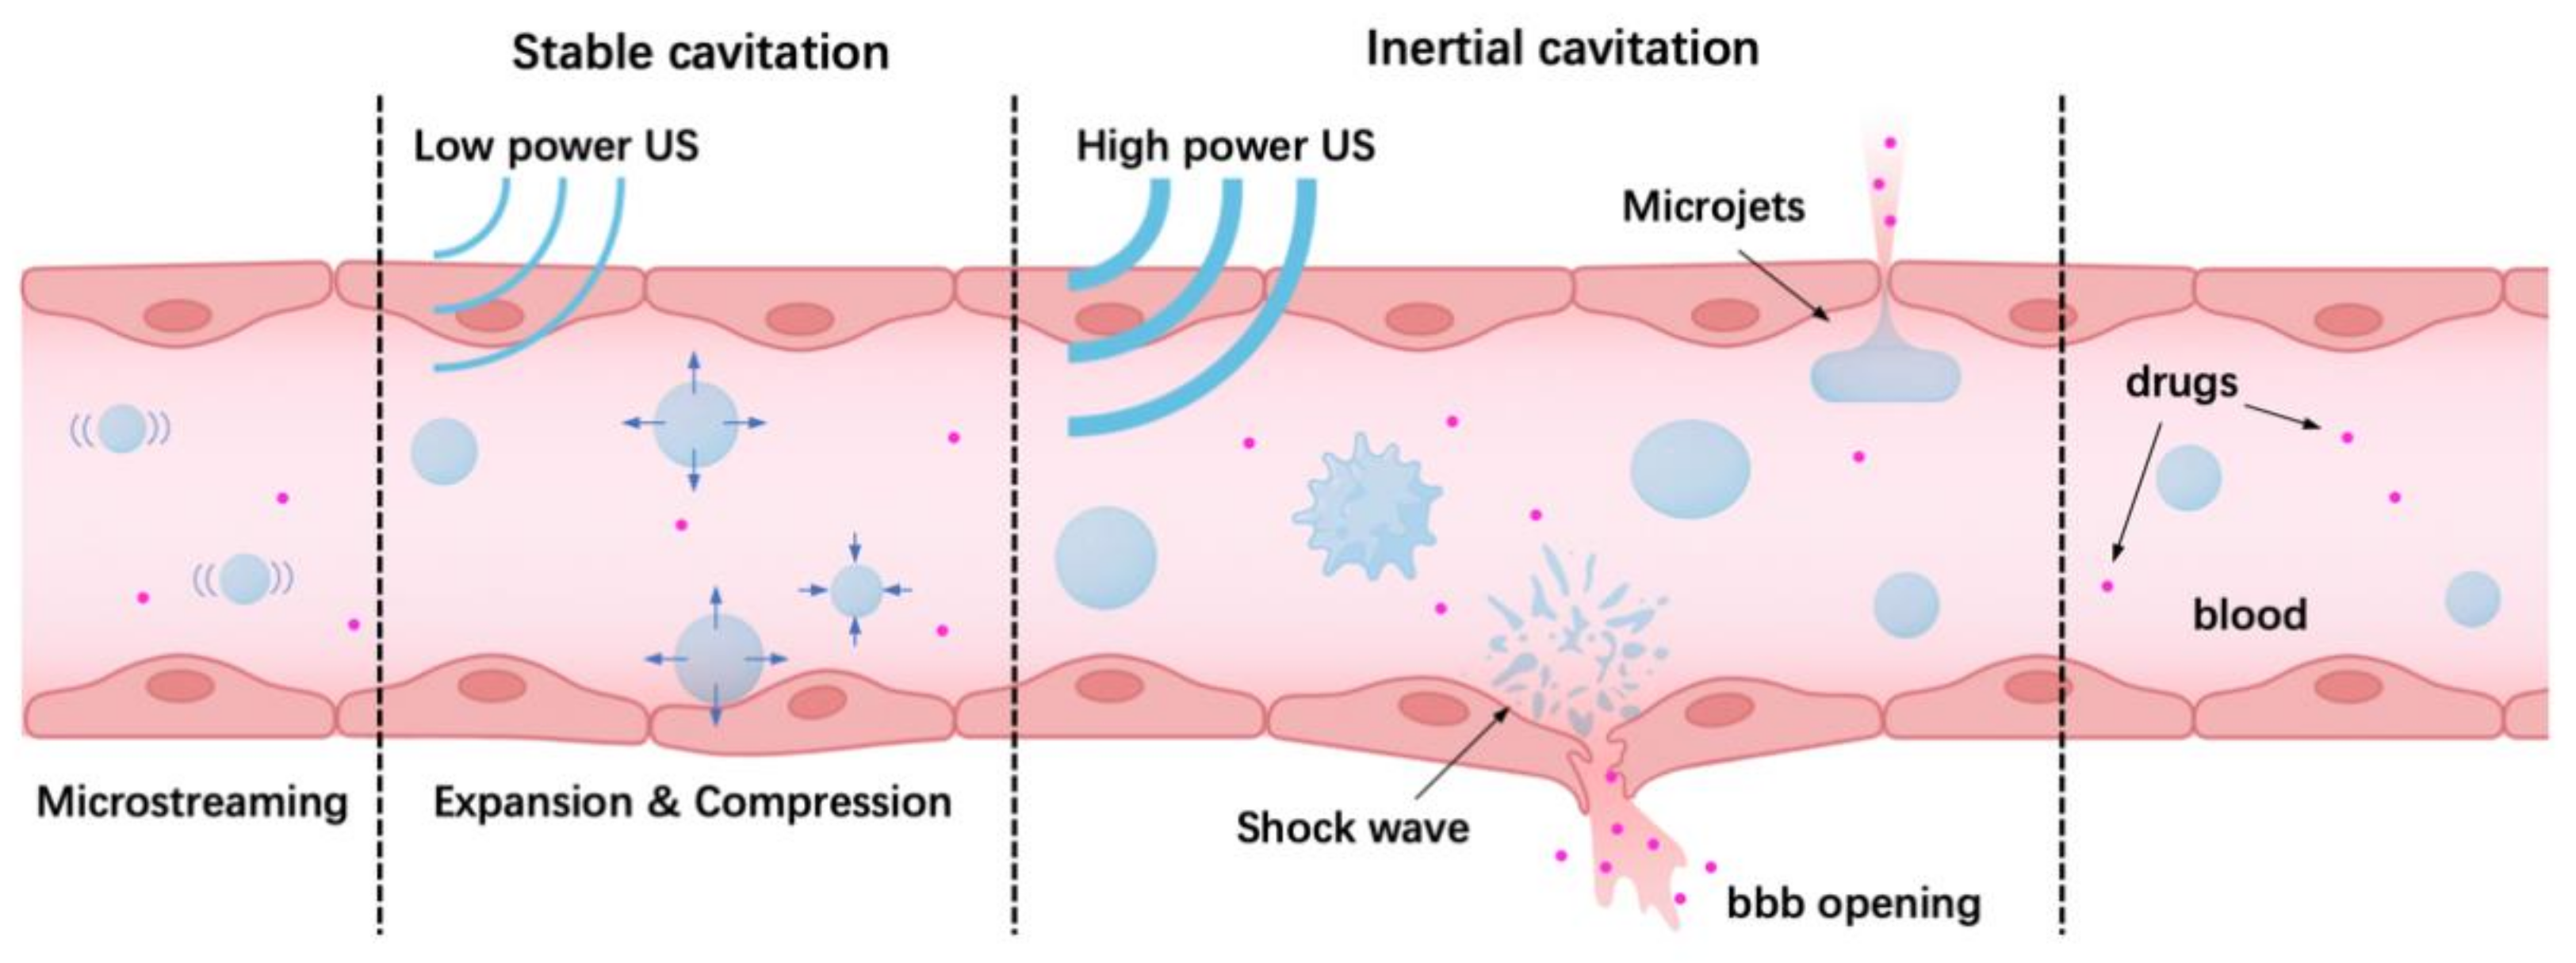

4.1. Oscillation and Cavitation of Microbubbles Driven by Ultrasound